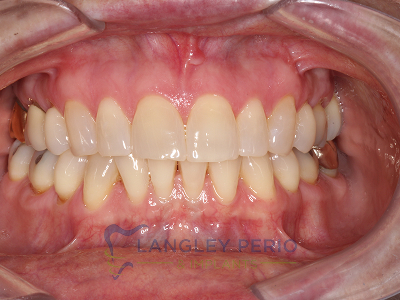

Case 2

Connective tissue grafting was done to cover exposed root surfaces to help to prevent root cavities from developing and reduce temperature sensitivity.